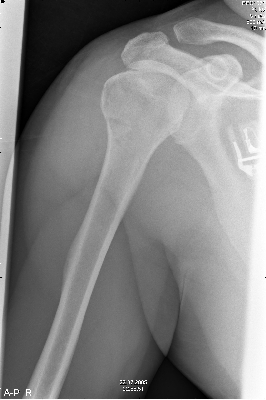

Nadat deze was terug gezet zag het er weer goed uit. |